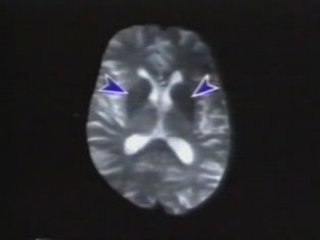

Emisión Especial 2021:br br Médicos de Japón lograron trasplantar células hepáticas derivadas de células madre embrionarias a un recién nacido que sufrió de una enfermedad de hígado.